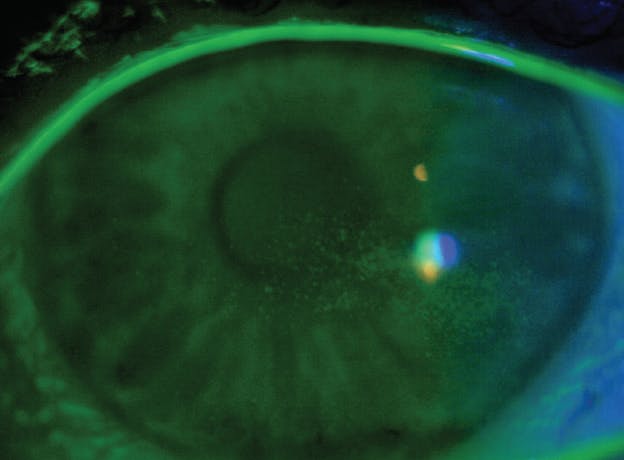

Autoimmune disease states are characterized by inflammatory outbursts throughout the body. Inflammation can often manifest on the ocular surface as part of the sequelae, seen as conjunctival injection and superficial punctate keratitis or erosions (Figure 1).

Figure 1. Punctate keratitis in inflammatory dry eye.